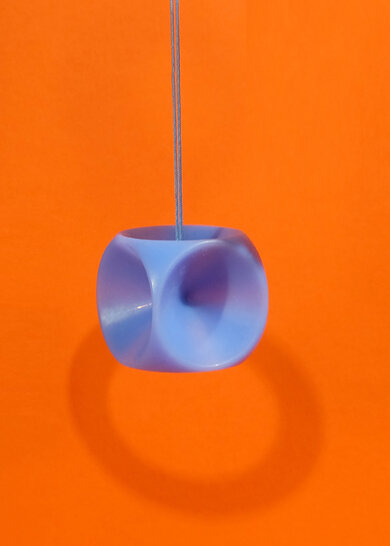

Keulen-/Glockenpessar

Ähnlich wie Schalen-Pessare, mit kleinem, keulenartigem Fortsatz, daher leicht zu entfernen. Sie kommen oft bei schwerer Inkontinenz zum Einsatz und müssen ebenfalls vor dem Geschlechtsverkehr entfernt werden.